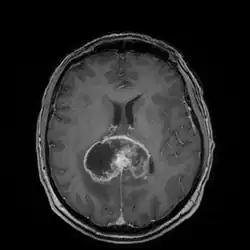

Die Diagnose wird zunächst durch bildgebende Verfahren wie Computertomographie (CT) oder Magnetresonanztomographie (MRT) gestützt. In der CT-Bildgebung mit Kontrastmittel erscheint das Glioblastom unregelmäßig geformt mit randständig starker Kontrastmittelaufnahme (ringförmiges Enhancement). Bei kleineren Tumoren ist dieses ringförmig konfiguriert, bei größeren bildet es eine girlandenartige Formation aus. In der Umgebung des Tumors bildet sich typischerweise ein erhebliches Ödem aus. Der MRT-Befund ist recht typisch: Die soliden Anteile des Glioblastoms reichern Kontrastmittel stark an, dagegen heben sich die Aussparungen durch zystische Anteile und die Blutungen ab. Letztendlich wird die Diagnose am Tumorgewebe, das bei einer stereotaktischen Hirnbiopsie oder Tumorresektion gewonnen wurde, neuropathologisch bestätigt. Im Einzelfall werden Supplementäruntersuchungen wie Elektroenzephalografie und Lumbalpunktion durchgeführt, die der Einschätzung der Anfallsneigung bzw. der differentialdiagnostischen Abgrenzung gegen Hirnabszesse oder Lymphome dienen.

Das Glioblastom ist durch seine inhomogene und vielfältige (daher: multiforme) Erscheinung gekennzeichnet: die Tumorschnittfläche weist häufig rötliche Einblutungen und gelbliche Gewebsuntergänge (Nekrosen) auf.